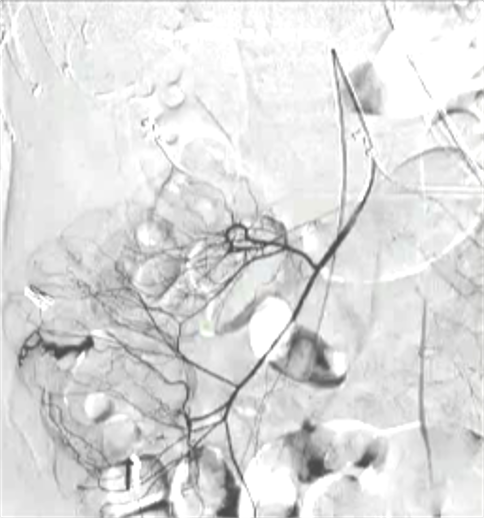

4. 技术要点急性消化道出血,生命体征稳定患者,CTA提示升结肠造影剂外溢

(1)操作流程·诊断性血管造影:用5F导管插管至肠系膜上/下动脉,寻找造影剂外溢(活动性出血)直接或间接征象 · · 超选择插管:通过同轴技术引入3F微导管,尽可能将导管送至直动脉(vasa recta) 或出血点最远端 · · 栓塞:首选微弹簧圈(2-3mm × 20-30mm),放置2-3个即可;也可用聚乙烯醇颗粒(>250μm);禁用液体栓塞剂(如酒精),因其肠坏死率高 · · 终点:造影证实外溢停止,同时保留近端和远端血流(不牺牲侧支循环) · (2)栓塞程度:多少算够?多少算多?理想情况:仅栓塞出血点所在的直动脉 若无法超选至直动脉,可栓塞边缘动脉(marginal artery),但必须确保:

o 近端和远端有足够的侧支血供

o 栓塞长度控制在3-4 cm以内(作者经验),避免过大范围缺血 o 栓塞的目标不是完全阻断血流,而是降低出血点的灌注压,配合局部血管痉挛和患者自身凝血能力形成血栓 5. 微导管远端栓塞临床数据:疗效与安全性一篇发表在2004年的文章汇总了12项研究【Brian Funaki 2004】、超过150例病例,核心数据如下: